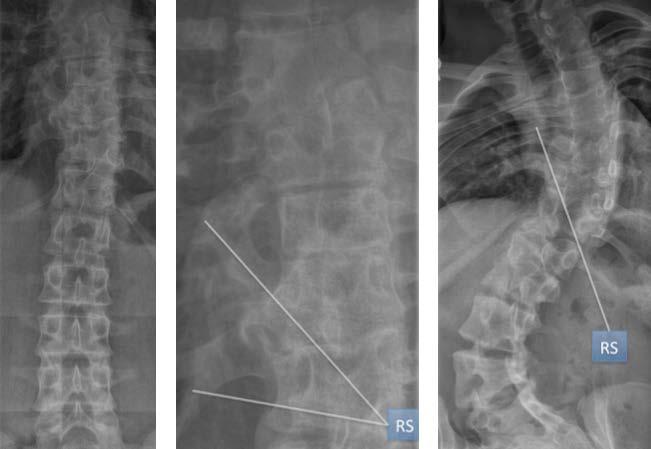

21 Abbildung 6: Spina Bifida, Neurofibromatosis, AMC (v. links nach rechts). Unterschiedliche Skolioseformen. Links gehfähiger Patient mit einer Meningomyelocele ohne Hautdefekt, aber mit deutlicher Haarbildung im Bereich der Haut über der Fehlbildung. Mitte: Thorakal rechtskonvexe Skoliose bei einem Jungen mit Neurofibromatose. Typisch sind Hautflecken, deren Farbe Milchkaffee ähnelt. Rechts Junge mit Arthrogryposis Multiplex Congenita (AMC) mit der typischen Kyphoskoliose. LESEPROBE

Bei den kongenitalen Skoliosen sind die Formationsstörungen (Keil-, Halbwirbel) von den Segmentationsstörungen (einseitige Stabbildung, Rippensynostosen) zu unterscheiden. Oft kommen Formationsstörungen gemeinsam mit Segmentationstörungen vor. Die kongenitalen Skoliosen sind vielfach gutartig und bedürfen oft überhaupt keiner Behandlung (Abbildungen 7 und 8). Segmentationsstörungen sind nicht immer progredient, auch wenn bei mehrsegmentalen Synostosen eher von einer ungünstigen Prognose ausgegangen werden muss (Abbildung 9). Vom klinischen Erscheinungsbild her sind kongenitale Skoliosen mitunter unauffällig (Abbildungen 7 und 8), können aber besonders im Zusammenhang mit Segmentationsstörungen zu beträchtlichen Deformitäten führen (Abbildung 10). Somit besteht auch bezüglich der symptomatischen oder syndromatischen Skoliosen primär eine konservative Behandlungsindikation, wobei auch hier in Phasen verstärkten Wachstums die Korsettversorgung und in Phasen geringerer Wachstumserwartung die spezifische Physiotherapie im Vordergrund steht (Weiss und Goodall 2009, Weiss 2012, Kaspiris et al. 2011). Die vielfach propagierte frühe operative Behandlung der kongenitalen Skoliose ist bei balancierten Deformitäten meist unnötig und bei größeren Deformitäten nicht grundsätzlich erfolgreich (Abbildung 11). Die hohe Komplikationsrate bezüglich der operativen Behandlung (Weiss und Goodall 2008) und die mangelnde Evidenz hinsichtlich postoperativer Langzeitverläufe bis zum Wachstumsabschluss (Kaspiris et al. 2011) sprechen gegen eine primäre operative Indikation bei Patienten mit kongenitaler Skoliose.

23 Abbildung 9: Zwei Patienten mit kongenitaler Skoliose und Rippensynostosen (RS). Die Wirbelsäule der Patientin auf der linken Seite ist nach weitgehend knöcherner Ausreifung trotz der nachgewiesenen Rippensynostosen fast gerade. Rechts mehrsegmentale Rippensynostosen mit ausgeprägter Deformität. LESEPROBE